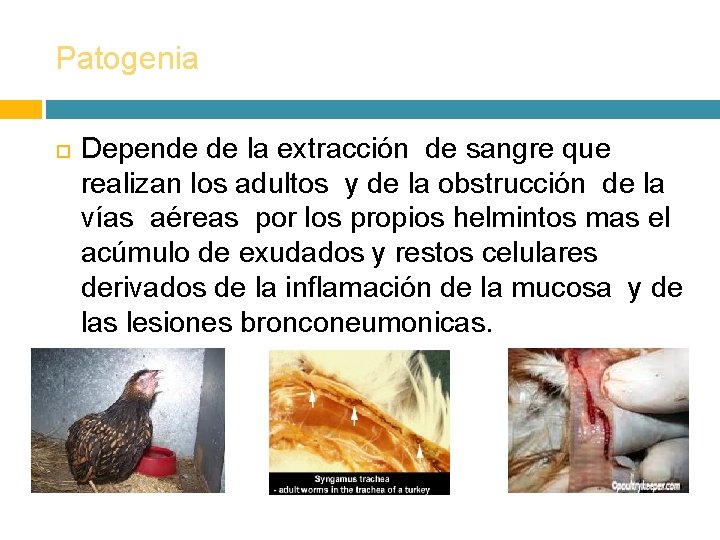

Patogenia Depende de la extracción de sangre que realizan los adultos y de la obstrucción de la vías aéreas por los propios helmintos mas el acúmulo de exudados y restos celulares derivados de la inflamación de la mucosa y de las lesiones bronconeumonicas.